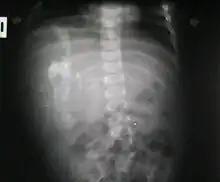

Radiografía anteroposterior abdominal.